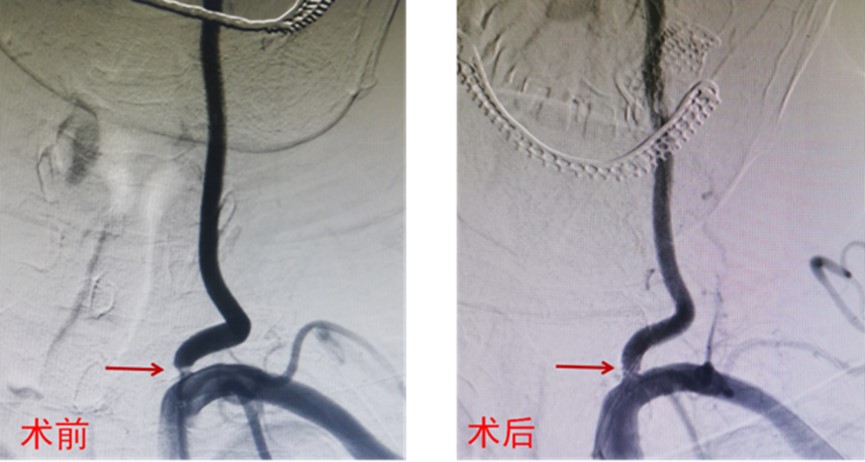

于2023-07-20行全脑血管造影术,术中造影显示左侧椎动脉优势,开口狭窄,最窄处狭窄率约90%;遂行左侧椎动脉支架置入术,支架置入顺利,手术很快结束(图1)。正当准备返回病房时,患者出现意识不清、右侧肢体无力。查体:神志昏睡,失语,右上肢肌力0级,右下肢肌力2级。什么原因造成了患者病情变化呢?

图1 DSA术前显示左侧椎动脉开口重度狭窄,术后左侧椎动脉显影良好